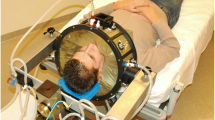

Hyperthermia was applied using the 70 MHz AMC‑4 phased array system [32], consisting of four waveguides with individual phase amplitude control to focus heating to the target location. Target temperatures were measured every 30 s using three 14-sensor thermocouple probes (0.5-cm spacing) mounted on a silicone elastomer mold applicator that fixates the thermometry probes in the vaginal cavity (Fig. 1). These temperatures at the apex of the vaginal cylinder are considered representative for the temperatures achieved in the tumor region, since locoregional hyperthermia yields a focal heating zone measuring a quarter of the wavelength in tissue, which is about 10–15 cm at 70 MHz. Additional thermometry probes for locoregional treatment control were positioned in the bladder and rectum. The steady-state period started when 41 °C was registered in the target, or after a 30-min induction period, whichever was shortest; steady-state was aimed for 60 min. Phase amplitude settings were optimized at the start of treatment and adjusted during treatment, if necessary, to avoid hotspot complaints, retaining tumor heating at the same level whenever possible [14, 15].

a Silicone elastomer mold applicator (diameter 25 mm) used to fixate intravaginal thermometry probes to measure target temperatures during hyperthermia treatments of cervical cancer patients. Three 14-sensor thermocouple probes (left, central, right) with 5‑mm sensor spacing are positioned along the grooves in the mold applicator. b The mold applicator and the thermocouple probes are covered with a condom before insertion into the patient’s vagina. c Hyperthermia planning CT scan in hyperthermia treatment position with thermometry in situ